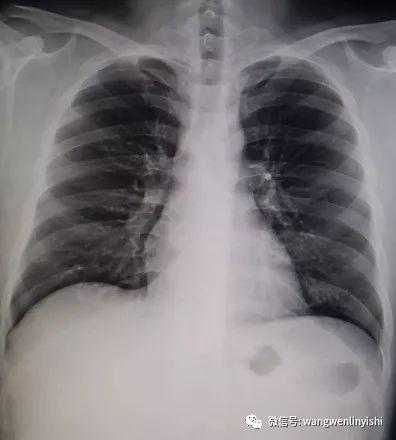

The upper part of the patient’s chest wall is protruded as a whole, coupled with depressions in the central and lower regions, presenting a classic example of Wenlin chest.

The Specificity of Wenlin Chest

Wenlin chest is a distinctive chest wall deformity that was often mistakenly identified as pectus carinatum in the past. However, unlike PC, which is characterized by a single protrusion, Wenlin chest involves both protrusions and depressions, classifying it as a kind of complex chest wall deformities. This malformation can not be corrected by traditional surgeries that work for PC. Notably, the depression in Wenlin chest is only apparent in comparison to the protrusion of the upper chest wall, without significantly compressing the patient’s heart.